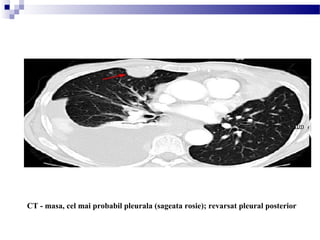

LOCALIZAREA MASEI

Intraparenchimatosa vs. pleurala vs. extrapleurala

A = intraparenchimatos

B = pleural

C = extrapleural

CT - masa, cel mai probabil pleurala (sageata rosie); revarsat pleural posterior

CT - distrugere osoasa , masa extrapleurala